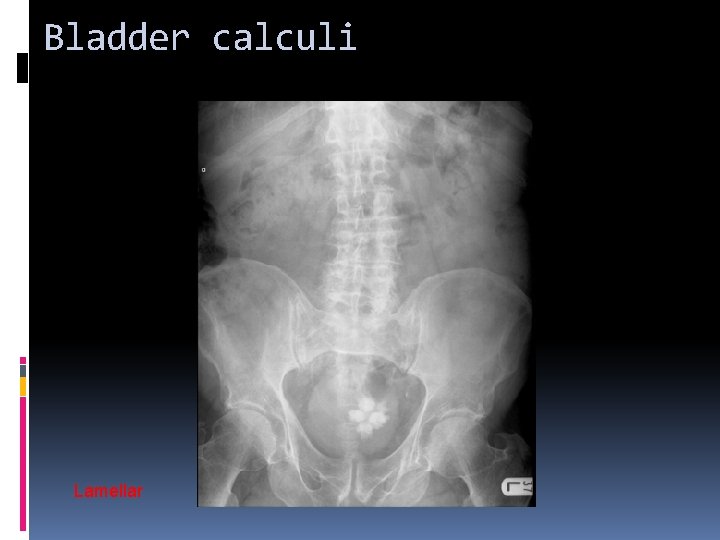

Bladder calculi Lamellar